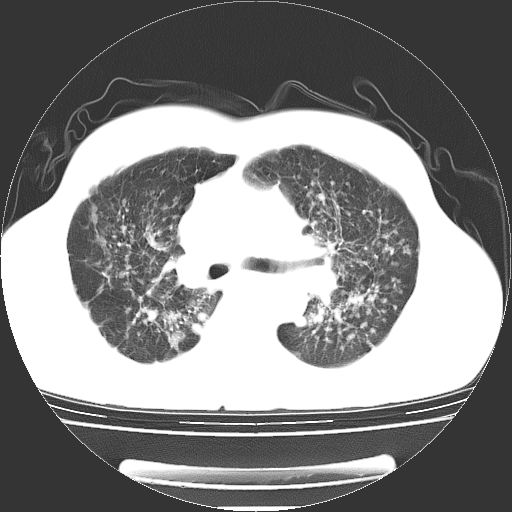

以下是引用yangyudong333在2008-4-29 5:38:00的发言:[br]比较典型的矽肺结节.支持[br]诊断依据:[br] 1.x线表现:[br] ①典型矽肺为多发直径 1~3mm 小结节,即矽结节,由胶原纤维和硅尘构成,可融合成团块,好发于上肺。[br] ②团块周围常有肺大泡。[br] ③胸内淋巴结增大、钙化。如肺门淋巴结呈蛋壳样钙化有助于与其他尘肺区别。[br] ④胸膜常广泛粘连、增厚。[br] 2.ct表现[br] ①两肺散在大小较为一致的小结节影,其密度较高,边界清楚。[br] ②小结节可融合为较大团块影,直径约 1cm ,甚至可达 10cm以上,易发生在上叶。[br] ③小结节周围常并有小叶中心气肿或弥漫性肺气肿。

以下是引用liuyue在2008-4-28 22:30:00的发言:[br]比较典型的矽肺结节.[br]请结合临床及化验除外矽肺合并肺结核之可能.